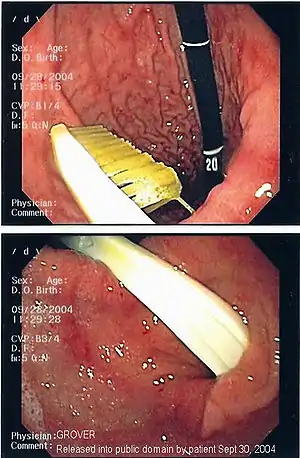

| آندوسکوپی نگاره یک جسم خارجی (مسواک) در شکم | |